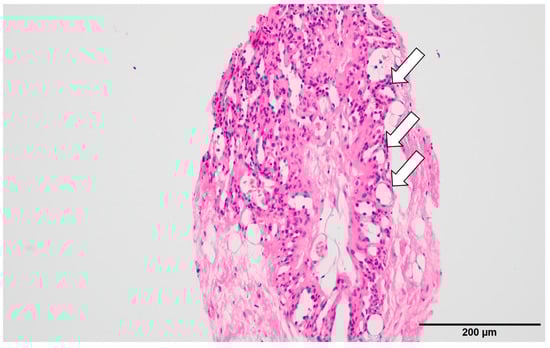

Histopathology demonstrated proliferation of small capillary-like vessels with extravasation of red blood cells, fibrin deposition, and partial fibrosis (Figure 6a,b). Endothelial cells showed no significant atypia. The initial biopsy specimen also showed small vessels within fibrous stroma. A final diagnosis of capillary hemangioma with slow enlargement over 11 years was made.

Figure 6. Histopathological findings (after 11 years): Hematoxylin–eosin staining of the vacuum-assisted biopsy specimen revealed clusters of small capillary-like vessels (arrows) with erythrocyte extravasation, fibrin deposition, and focal fibrosis (a,b). The endothelial cells exhibited no significant atypia. Similar findings were noted in the initial biopsy specimen, confirming a diagnosis of capillary hemangioma with gradual enlargement over 11 years.